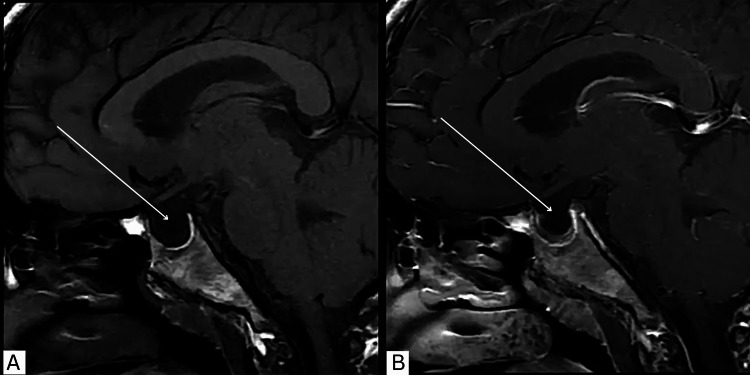

特发性颅内高压(IIH)和多囊卵巢综合征(PCOS)与育龄妇女肥胖密切相关。胰高血糖素样肽-1受体激动剂(GLP-1 RAs)已被广泛报道通过中枢饱腹感促进体重减轻。新出现的证据表明GLP-1 RAs具有额外的益处。艾塞那肽直接作用于脉络膜丛受体,减少脑脊液(CSF)分泌和颅内压(ICP),并作用于卵巢,促进卵泡成熟,恢复排卵,改善PCOS患者的生育结局。一位29岁女性多囊卵巢综合征被转介到妇科评估间歇性视力模糊和慢性头痛。眼科检查单眼视力正常6/5,双眼视力下降6/12,伴重影。据报道,她在8个月内体重增加了15公斤。眼底镜检查无明显异常,无视盘肿胀。无乳头水肿(iihop)的诊断是基于磁共振成像显示垂体窝增大,部分鞍空,视神经鞘扩张,腰椎穿刺证实开口压力升高280 mmH₂O,脑脊液正常。最初使用乙酰唑胺治疗因不耐受而停止。随后开始使用艾塞那肽,导致头痛频率和复视的早期改善,独立于体重减轻。月经周期、激素水平和胰岛素抵抗的改善也超出了单用二甲双胍的效果。该病例强调了艾塞那肽在IIH和PCOS中提供双重治疗益处的潜力,通过直接受体介导的途径降低ICP,改善头痛,恢复排卵周期,并间接通过减少中心性肥胖。有必要进行进一步的研究,以确定其在这些条件的联合管理中的作用。

Idiopathic intracranial hypertension (IIH) and polycystic ovary syndrome (PCOS) are strongly associated with obesity in women of reproductive age. Glucagon-like peptide-1 receptor agonists (GLP-1 RAs) have been extensively reported to facilitate weight loss through central satiety. Emerging evidence demonstrates additional benefits of GLP-1 RAs. Exenatide exerts direct effects on choroid plexus receptors, reducing cerebrospinal fluid (CSF) secretion and intracranial pressure (ICP), and on the ovary, enhancing follicular maturation, restoring ovulation, and improving fertility outcomes in PCOS. A 29-year-old woman with PCOS was referred from gynecology for assessment of intermittent visual blurring and chronic headaches. Ophthalmic examination revealed normal monocular visual acuity of 6/5 in each eye but reduced binocular vision of 6/12, associated with double vision. She also reported a weight gain of 15 kg over eight months. Fundoscopy was unremarkable, with no optic disc swelling. IIH without papilledema (IIHWOP) was diagnosed based on magnetic resonance imaging showing an enlarged pituitary fossa, partial empty sella, and optic nerve sheath dilatation, with lumbar puncture confirming a raised opening pressure of 280 mmH₂O and normal CSF. Initial treatment with acetazolamide was discontinued due to intolerance. Exenatide was subsequently initiated, leading to early improvement in headache frequency and diplopia, independent of weight loss. Menstrual cycles, hormonal profile, and insulin resistance also improved beyond the effect of metformin alone. This case highlights the potential of exenatide to provide dual therapeutic benefits in IIH and PCOS, acting through direct receptor-mediated pathways to reduce ICP, improve headaches, and restore ovulatory cycles, and indirectly through the reduction of central obesity. Further studies are warranted to establish its role in the combined management of these conditions.